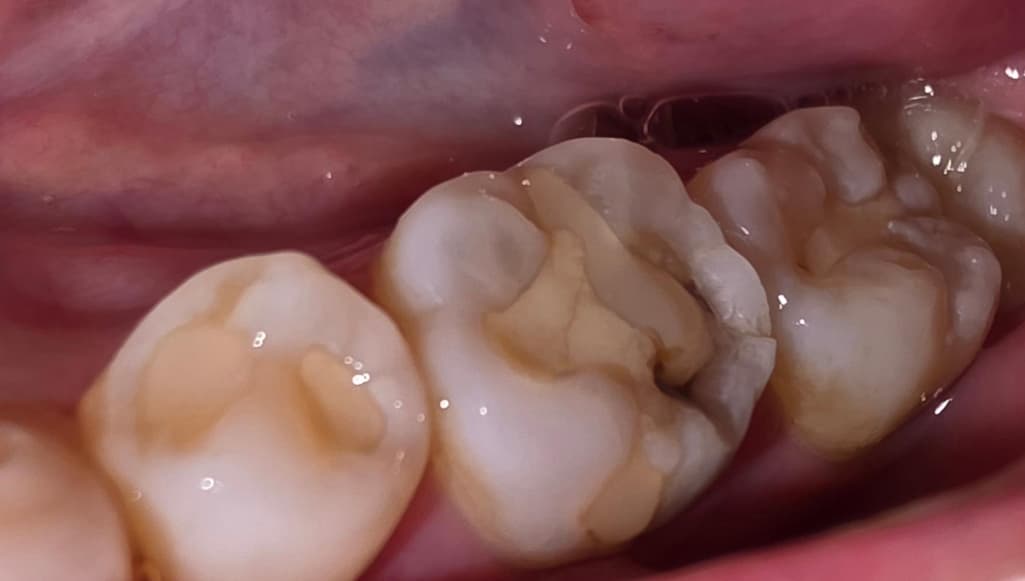

육포를 씹다가 갑자기 왼쪽 아랫부분 어금니가 욱신거리고 너무 아파서 카메라로 보니까 때운 부분이 저렇게 되어있던데 혹시 치아에 금이 간 건가요? ㅠㅠ

떼운부위가 깨져보이고 안쪽으로 충치가 생겼을수도 있고 치아에 금이 갔을수도 있으니 치과에 내원하여 확인하면 좋을것같습니다. 빠른 회복 바라겠습니다. 건강하세요.

떼운 부위가 깨져나갔네요, 사진상으로 봐서 명확하진 않으나 깨져나간 부위 외에도 금이 간 것처럼 보이기도 합니다. 치과 가보시기 바랍니다.

사진으로 봤을 경우에는 이전에 치과용 재료로 충전한 부분 주변에 충치가 생기면서 깨진 것으로 보입니다. 이런 경우 충치치료가 필요할 수 있습니다.

자세한 확인을 위해서 치과에서 진료를 받아보는 것을 권유드립니다.